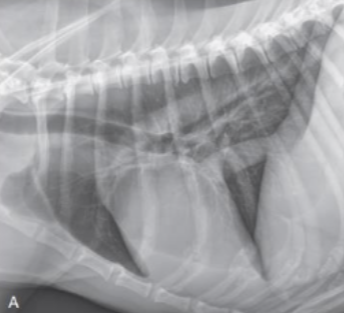

| VHS | Vertebral heart score.![]() | ์ฌ์ฅ ํฌ๊ธฐ์ ์ฒ์ถ๋ผ์ ๋น๊ต. - ์ฅ์ถ : carina์ ventral border์์ ์ฌ์ฅ์ apex๊น์ง (fat ํฌํจํ๋ฉด ์ ๋จ) - ๋จ์ถ : ์ฅ์ถ๊ณผ ์์งํ๊ฒ, CVC ๊ทผ์ฒ์์ ๊ฐ์ฅ ๋์ ๋ฒ์ โ T4 ๋งจ ์์ชฝ๋ถํฐ ์ฅ์ถ/๋จ์ถ ๊ธธ์ด๋งํผ ๊ฐ์ ๋ ์ฒ์ถ๋ผ์ ๊ฐ์๋ฅผ ๋ํจ. Dog : 8.5 Cat : 6.7 |